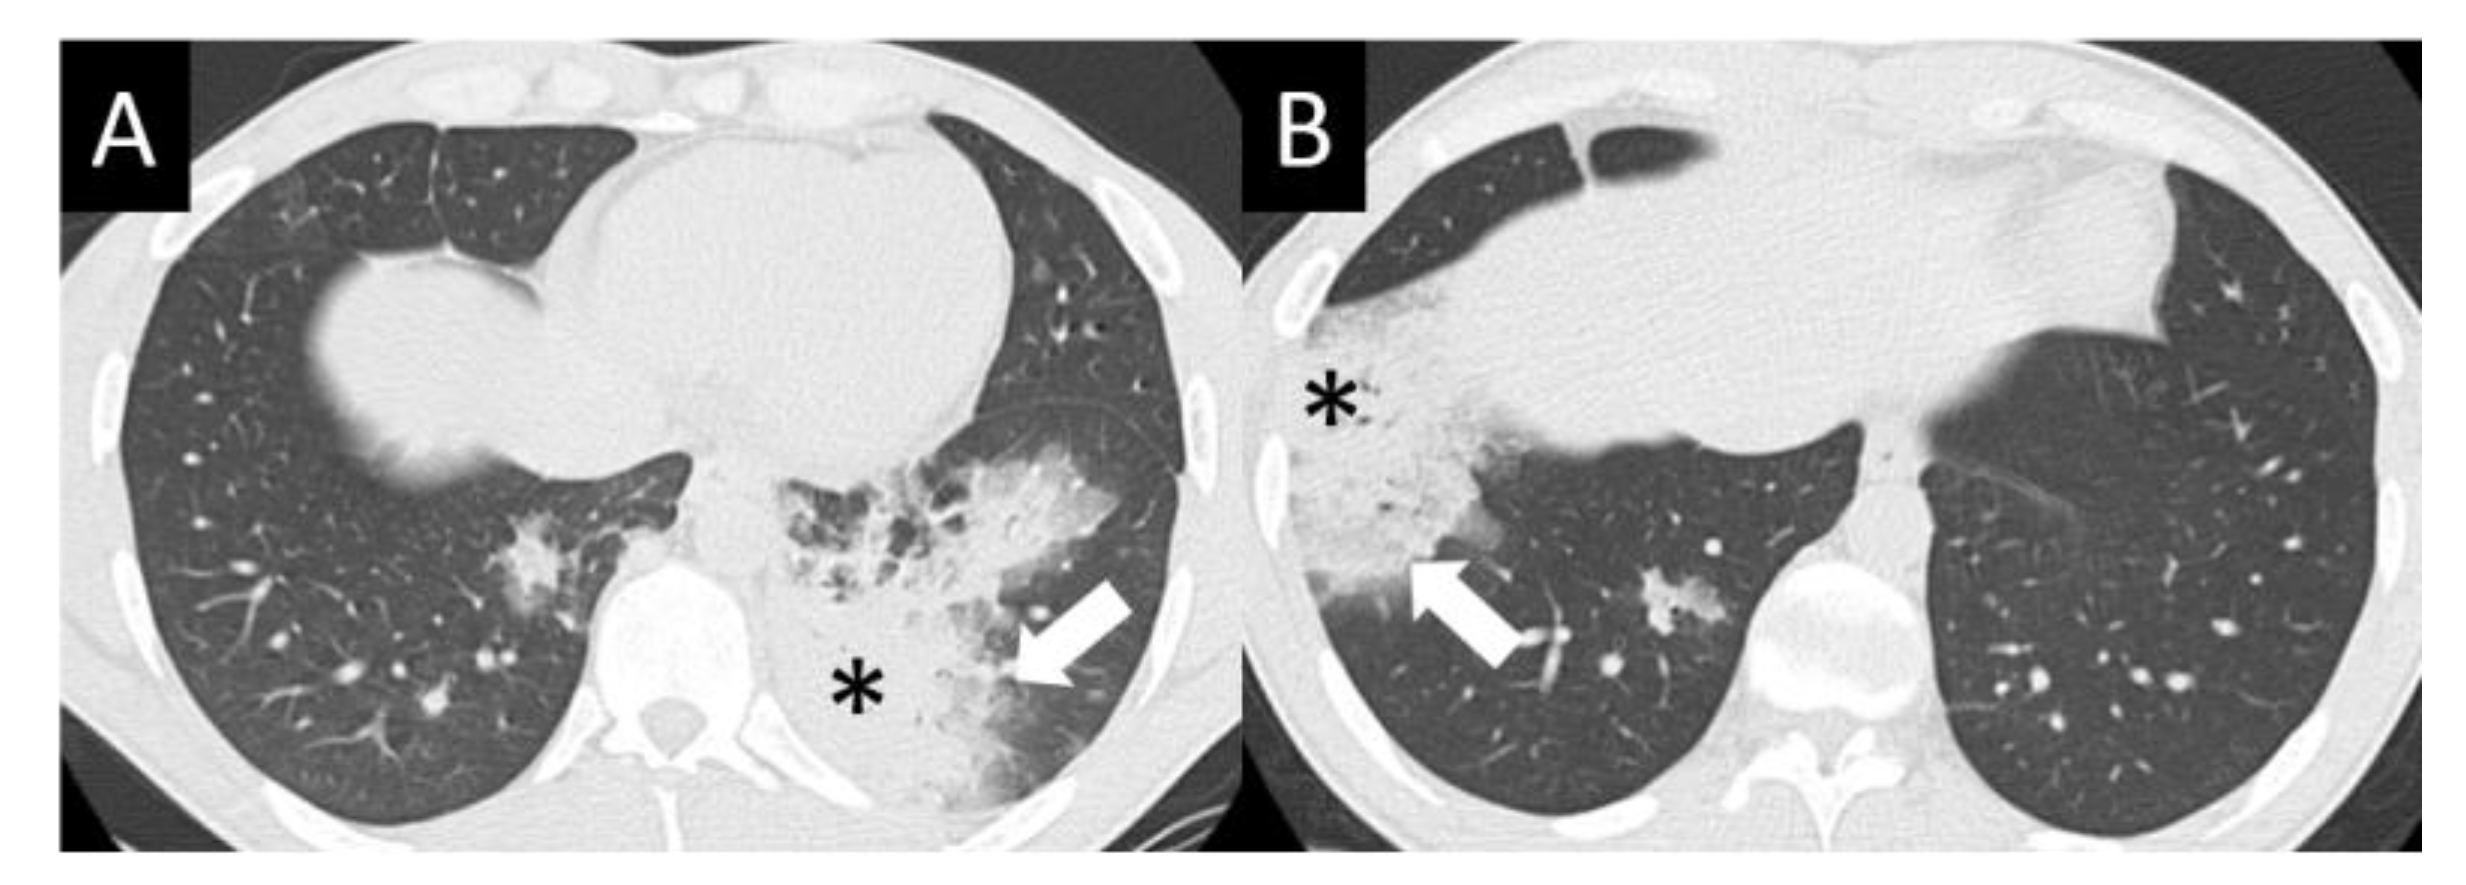

6.1.4. Chest Imaging

- Johkoh, T.; Lee, K.S.; Nishino, M.; Travis, W.D.; Ryu, J.H.; Lee, H.Y.; Ryerson, C.J.; Franquet, T.; Bankier, A.A.; Brown, K.K.; et al. Chest CT diagnosis and clinical management of drug-related pneumonitis in patients receiving molecular targeting agents and immune checkpoint inhibitors: A position paper from the Fleischner Society. Chest 2021, 159, 1107–1125. [Google Scholar] [CrossRef] [PubMed]